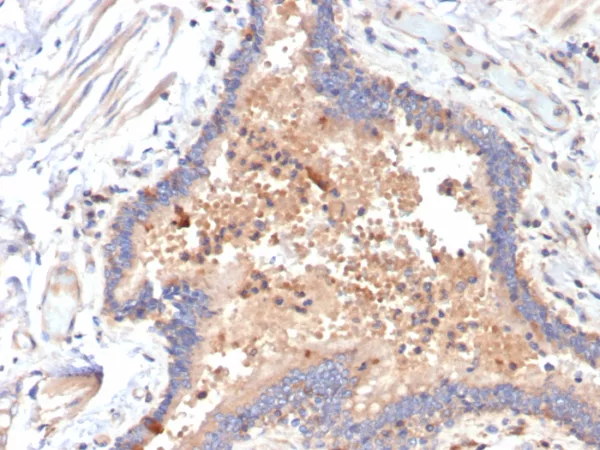

Formalin-fixed, paraffin-embedded human pancreas stained with IL-6 Mouse Monoclonal Antibody (IL6/4642) at 2ug/ml. Inset: PBS instead of primary antibody; secondary only negative control.